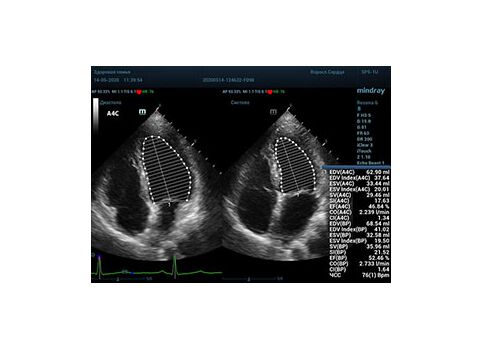

С появлением В режима реализовалась возможность визуализации всех сегментов миокарда из парастернальных и апикальных сечений. Метод Teicholtz в широкой практике сменился методом дисков. Метод дисков, или метод Simpson, позволяет разбить левый желудочек на 20 дисков, с расчетом объема каждого из них. Используя 2 перпендикулярных сечения, апикальные двух и четырех камерное, мы приближаемся к значению реального объема левого желудочка. Исследователь обводит интерфейс эндокард – кровь в фазу диастолы и фазу систолы. Линия простирается от кольца митрального клапана и до кольца митрального клапана, четко разграничивая объем желудочка от предсердия. Для достоверного изменения необходимо использовать ЭКГ канал.

Обводить вручную эти линии занимало много времени, однако результат того стоил. Следующим шагом стало появление Spline технологии, позволяющее расставлять точки и автоматически их соединять. Такой способ планиметрии контура эндокарда значительно сократил время измерения.

Что могут предложить современные приборы? Приборы нашего времени являются мощными вычислительными машинами, способными обрабатывать полученную информацию даже без помощи человека. Система автоматического вычисления фракции выброса – AUTO EF на

приборах серии Resona компании Mindray сделает все за вас. За пару секунд прибор сам отыщет нужную фазу сердечного цикла и произведёт измерение и расчеты, а также покажет график изменения объема в сердечном цикле. От Вас требуется только получить качественное 4С и 2С сечение. Впрочем, прибор всегда оставляет возможность коррекции, если доктор имеет свое мнение на расположение точек планиметрии или момента измерения по ЭКГ каналу.